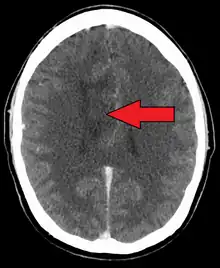

| A oligoastrocytoma on CT | |

An X-ray computed tomography (CT) or magnetic resonance imaging (MRI) scan is necessary to characterize the anatomy of this tumor as to size, location, and its heter/homogeneity. However, final diagnosis of this tumor, like most tumors, relies on histopathologic examination (biopsy examination).[3]